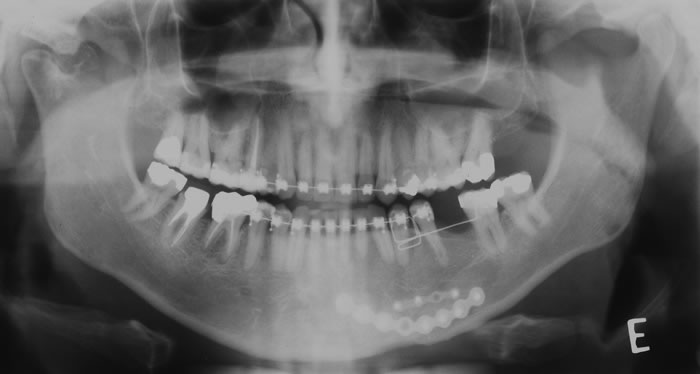

CASO 2 - Localização de dente retido

História clínica de exodontia do dente 38 há um ano, sem no entanto localizar o elemento dentário acreditando que o paciente havia engolido o dente. Na radiografia panorâmica observa-se a presença do dente 38 superposto ao ramo. Na tomografia localiza-se o dente no assoalho bucal.